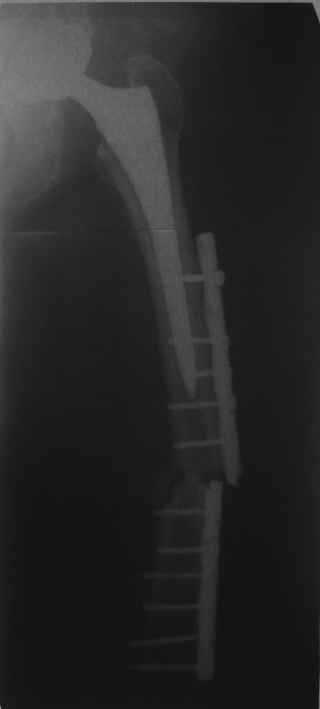

Re: Перипротезный перелом

Хотел бы обратить Ваше внимание, что реакция кортикала наблюдается только вокруг проксимального винта, дистальный винт не испытывает подобной нагрузки. Отсюда еще одна умозрительная авантюра - выкрутить только проксимальный винт. Изменения кости вокруг дистального винта тоже могут дать ответ на счет интеграции ножки, также как и появляется возможность сломать его. Страховаться (затратнее, но надежнее) или нет(легче, но не безопасно) динамическим винтом - на Ваш выбор.

О качестве сращения перелома тоже сказать трудно. Выраженной мозоли нет. В боковой проекции отломки накладываются друг на друга. В прямой проекции зона перелома в наружной части закрылась не полностью. Возможно причина тому - недогрузка кости.

Это сплошной титановый стержень. На дистальном конце отверстия под кондуктор. На другом - канал под ножку глубиной 60 мм, стенки толщиной 2,5-3 мм. И там же продольный пропил, чтобы канал мог адаптироваться к ножке.

Обещанные ранее снимки Заранее спасибо.